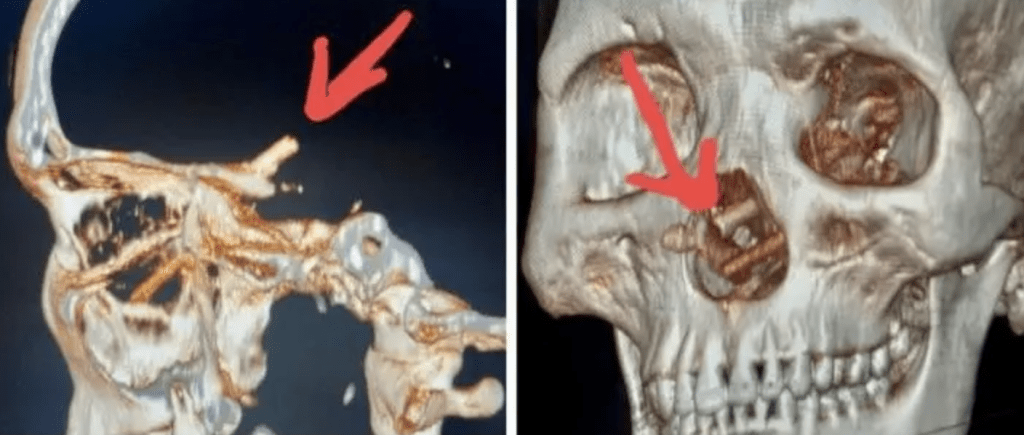

▲电脑断层扫描显示,男子颅腔内竟一双筷子。

医生为他进行CT 扫描,诊断出他患有压力性气脑,这是一种罕见但会危及性命的神经系统疾病,其特征是颅内压危险升高,成因一般为颅骨骨折,导致脑中出现游离气体。而最叫人震惊的是,扫描发现他颅内竟然有一双断折了的筷子,由鼻腔直插入内,匪夷所思。